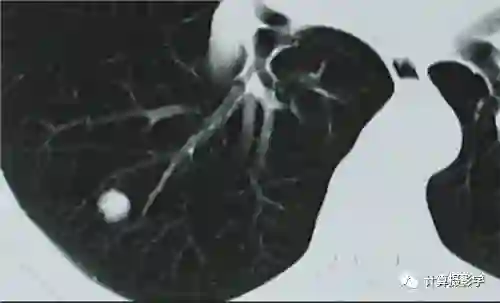

下面这张CT图片从美学上毫无美感,但是却能够清晰的揭示肺部的结节,它的图像质量高吗?